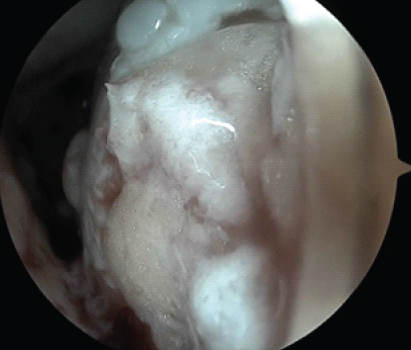

Figure 3: Arthroscopic image of the medial femoral condyle after delivery of the minced cartilage into the cartilage defect.

We initiated the arthroscopic autologous MCI technique with a diagnostic arthroscopy to assess the cartilage defect. Healthy cartilage was then arthroscopically harvested from the defect using a soft tissue shaver connected to an autologous tissue collector (GraftNet: Arthrex), ensuring minimal enlargement of the defect after preparation. The calcified layer was removed, but subchondral drilling was not performed. The harvested cartilage was minced into small fragments, resulting in a paste-like consistency. Minced cartilage was then mixed with platelet-rich plasma (PRP) in a 1:3 ratio. The resulting mixture was loaded into an applicator. Autologous thrombin was generated from additional PRP using a specific device (Thrombinator: Arthrex). After thoroughly drying the joint, the defect was filled with the cartilage-PRP mixture using the applicator. Following a short waiting period, the knee joint was moved through a range of motion to confirm graft fixation over the chondral defect (Fig. 1, 2, 3, 4).